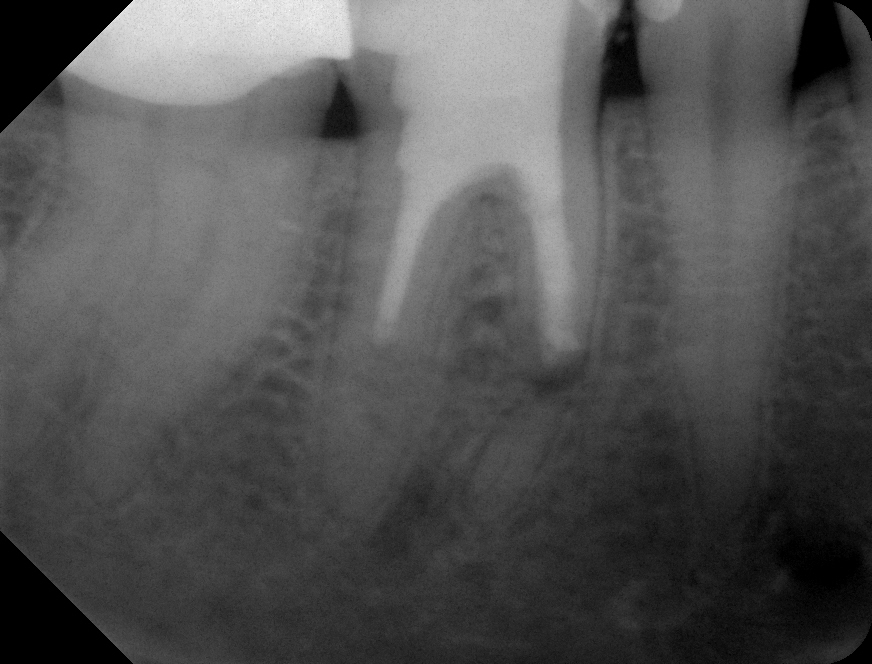

08 – Zahn 46 – WF + apikaler Verschluss Veröffentlicht 2. Juli 2013 am 872 × 664 in Wurzelresorption mal anders